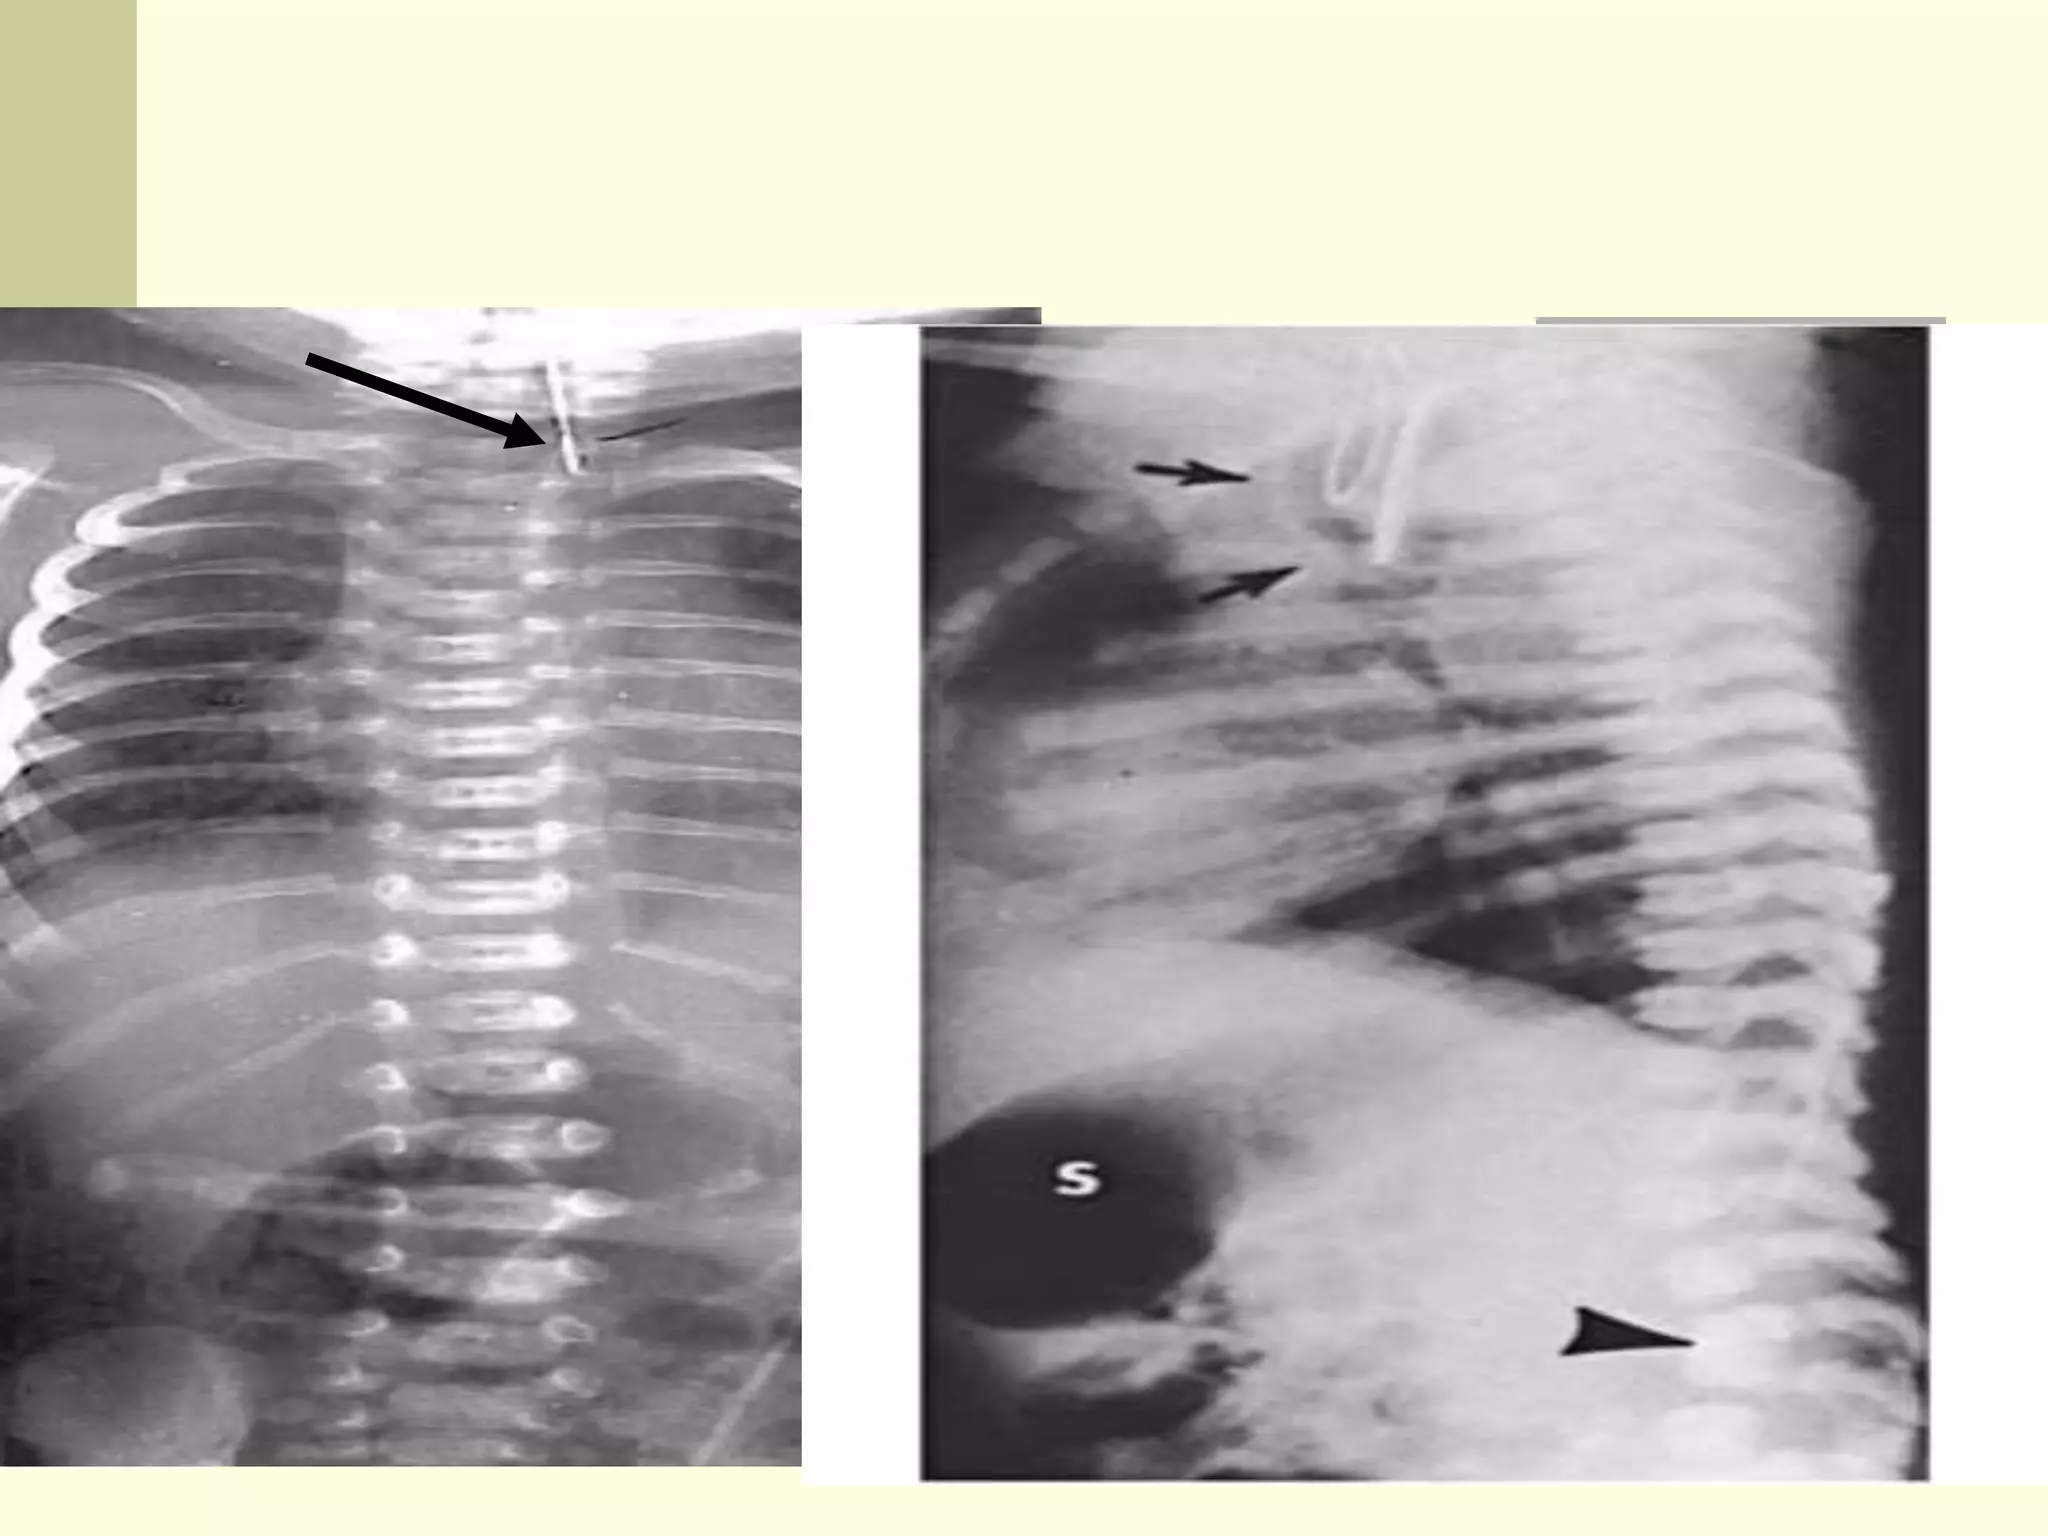

1) Plain AP – Lat radiograph

with

stiff red rubber catheter in situ

 Conform the level of atresia ( upper pouch)

in term of thoracic vertebra.

 Check the presence of abdominal gas to rule

out the pure esophageal atrisia

 Asses the pulmonary shadow to rule out

pneumonia or Pneumonitis

 Assess the cardiac shadow and calculate the

C.P ratio to suspect cardiac anomalies